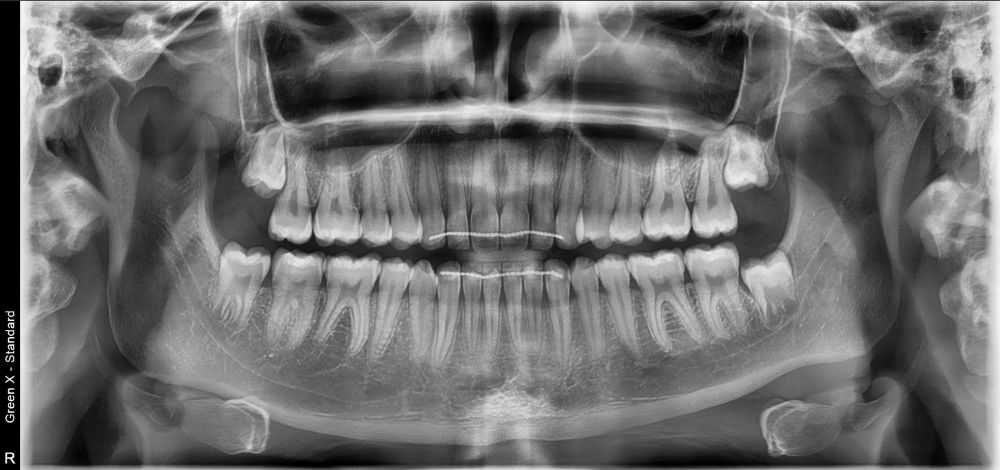

- wyraźne obrazy 2D i 3D — pomocne przy implantach, ósemkach, leczeniu kanałowym i ortodoncji

Pantomogram pokazuje cały stan uzębienia i kości — dzięki temu można wykryć zmiany, których nie widać na małym zdjęciu punktowym (jak torbiele, stany zapalne czy problemy ze stawami). To proste badanie, które warto wykonać profilaktycznie co kilka lat.